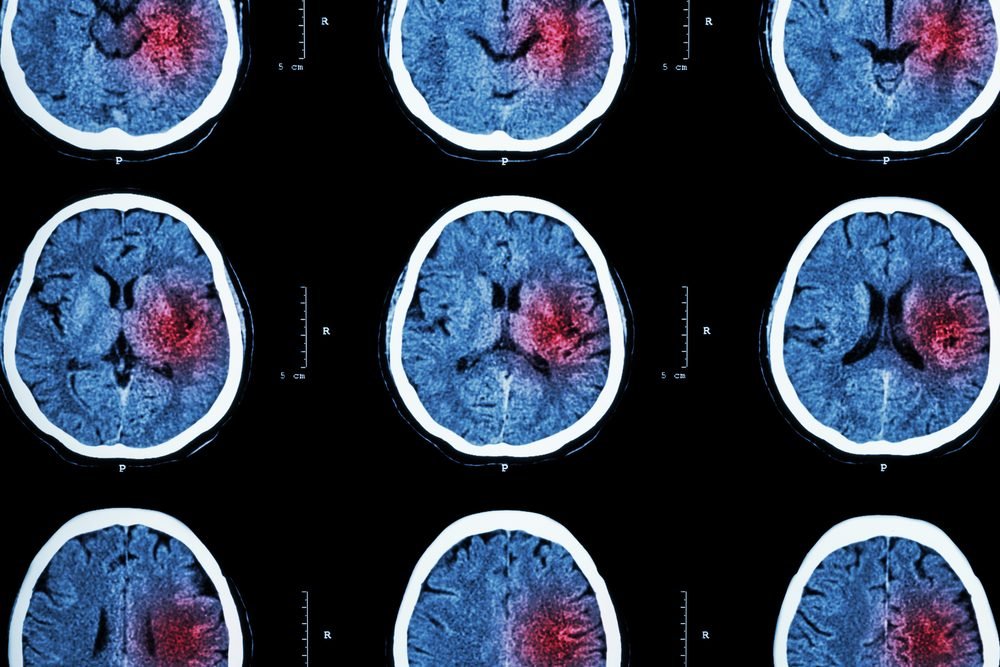

Black Americans face a significantly higher risk of stroke compared to their White counterparts, often experiencing these life-threatening events at younger ages. Strokes remain a leading cause of death and disability across the United States, and recent research highlights stark disparities in incidence rates between racial groups. Studies analyzing decades of hospital data from Ohio and Kentucky show that while the overall rate of stroke has declined over time, Black adults continue to experience strokes at a rate nearly 50 to 80 percent higher than White adults. Alarmingly, these strokes often occur almost a decade earlier for Black adults, amplifying the long-term health and social consequences for individuals and communities.

Several medical and social factors contribute to the elevated stroke risk among Black Americans. Hypertension, high cholesterol, diabetes, and obesity are prevalent in this population and are well-known contributors to cerebrovascular disease. Preeclampsia, gestational hypertension, and other pregnancy-related complications further increase the risk for Black women. Additionally, socioeconomic factors, including limited access to quality healthcare, disparities in treatment, and systemic stressors such as discrimination, compound these health risks. Collectively, these elements create a scenario where Black Americans not only experience strokes more frequently but also face greater challenges in recovery and prevention.